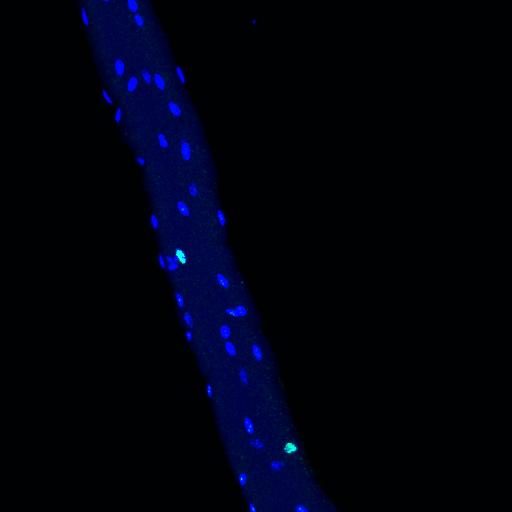

Usually, each cell has exactly one nucleus. But the cells of our skeletal muscles are different: These long, fibrous cells have a comparatively large cytoplasm that contains hundreds of nuclei. But up to now, we have known very little about the extent to which the nuclei of a single muscle fiber differ from each other in terms of their gene activity, and what effect this has on the function of the muscle.

A team led by Professor Carmen Birchmeier, head of the research group on Developmental Biology / Signal Transduction at the Max Delbrueck Center for Molecular Medicine in the Helmholtz Association (MDC), has now unlocked some of the secrets contained in these muscle cell nuclei. As the researchers report in the journal Nature Communications , the team investigated the gene expression of cell nuclei using a still quite novel technique called single-nucleus RNA sequencing - and in the process, they came across an unexpectedly high variety of genetic activity.

The researchers began by studying the gene expression of several thousand nuclei from ordinary muscle fibers of mice, as well as nuclei from muscle fibers that were regenerating after an injury. The team genetically labeled the nuclei and isolated them from the cells. "We wanted to find out whether a difference in gene activity could be observed between the resting and the growing muscle," says Birchmeier.

And they did indeed find such differences. For example, the researchers observed that the regenerating muscle contained more active genes responsible for triggering muscle growth. "What really astonished us, however, was the fact that, in both muscle fiber types, we found a huge variety of different types of nuclei, each with different patterns of gene activity," explains Birchmeier.